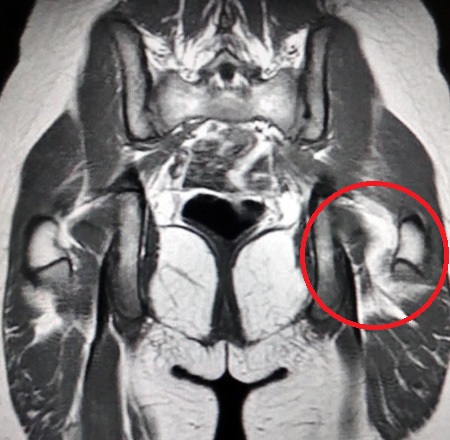

Christyna Suffers Severely (Grade 3) Ruptured Hip Flexor

MRI Torn Hip Flexor